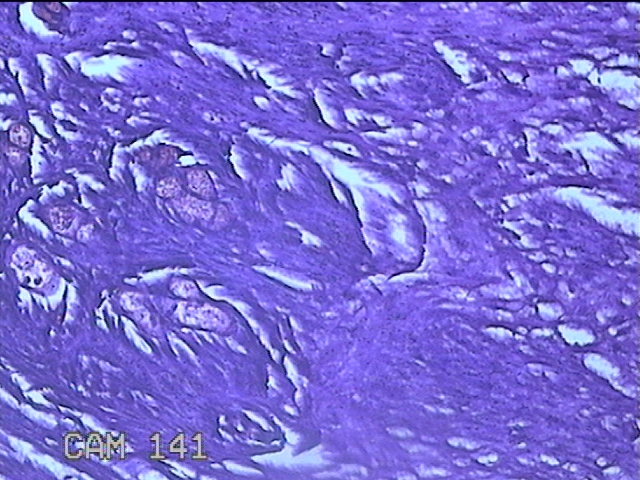

咽部肿物

临床诊断

一般病史

反复咽异物感不适1月。

标本名称

大体所见

灰白粉红色肿物0.8x0.5x0.2cm一个,表面光滑。

图3